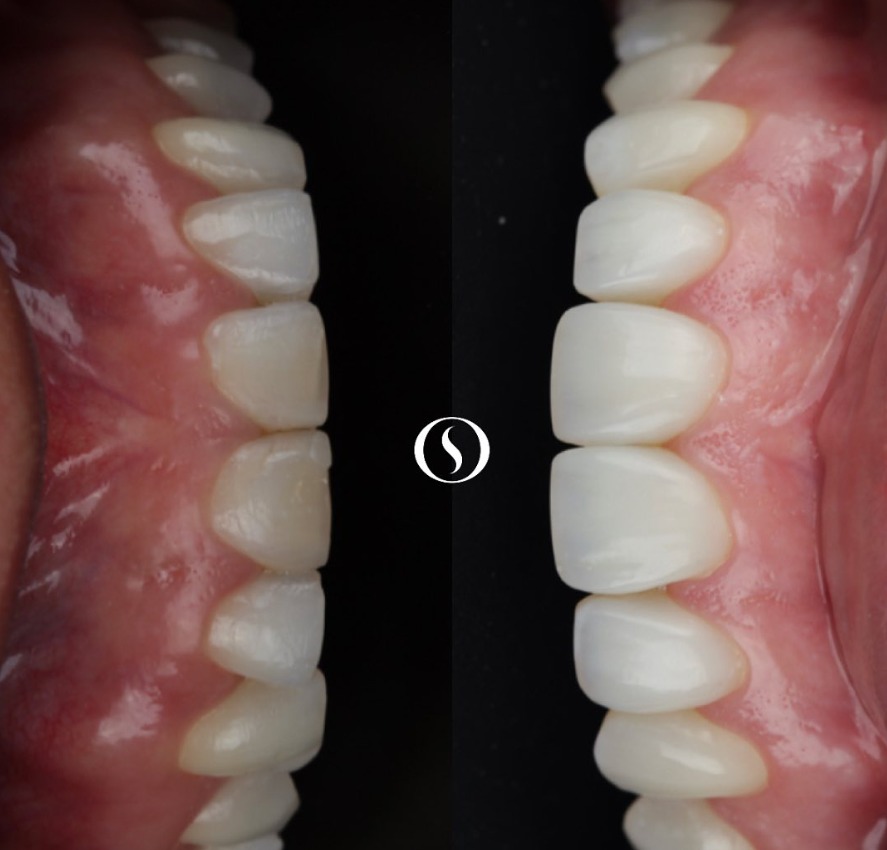

A implantodontia é um procedimento odontológico que envolve a colocação de implantes dentários de titânio no osso maxilar ou mandibular para substituir dentes perdidos. Os implantes proporcionam uma base sólida para a fixação de coroas, pontes ou próteses, restaurando a função mastigatória, estética e saúde bucal do paciente.